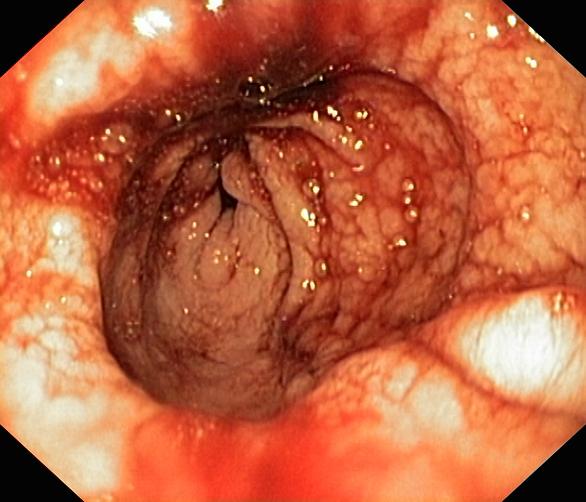

Krwawienie